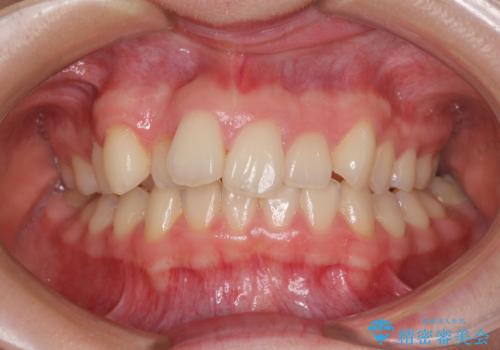

- 上顎前歯のデコボコを気にして来院された患者様です。

口元の突出感はなく、上顎のみに顕著な叢生が認められました。